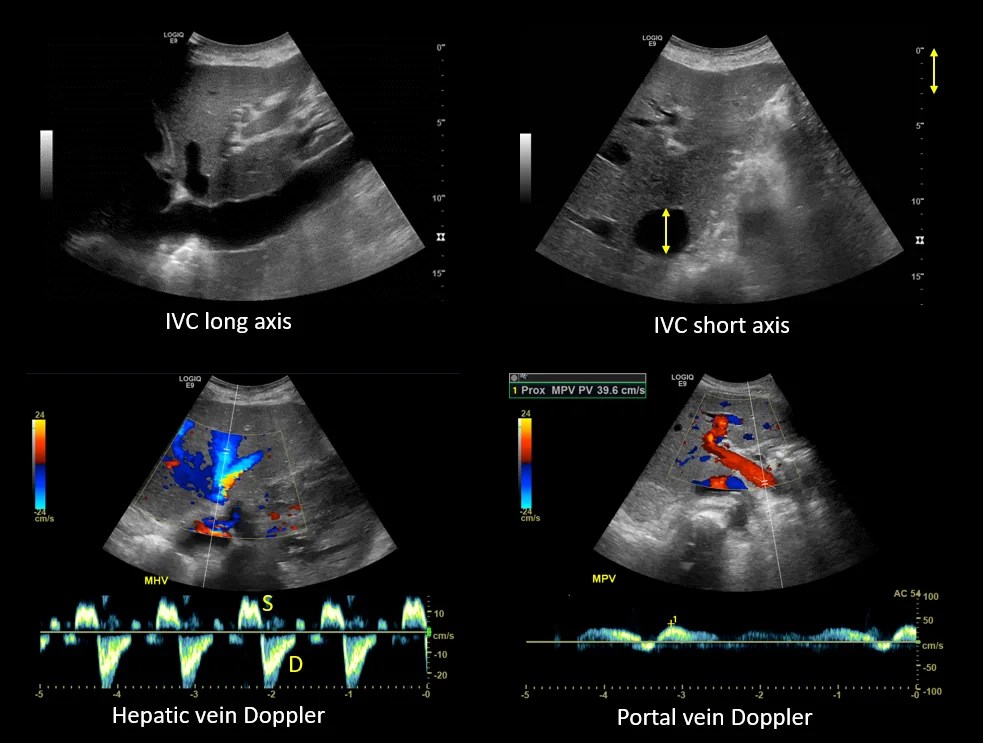

Figure 2. Venous excess ultrasound grading: When the diameter of the inferior vena cava is > 2 cm, three grades of congestion are defined based on the severity of abnormalities on hepatic, portal, and renal parenchymal venous Doppler. Hepatic vein Doppler is considered mildly abnormal when the systolic (S) wave is smaller than the diastolic (D) wave, but still below the baseline; it is considered severely abnormal when the S-wave is reversed. Portal vein Doppler is considered mildly abnormal when the pulsatility is 30% to 50%, and severely abnormal when it is ≥ 50%. Asterisks represent points of pulsatility measurement. Renal parenchymal vein Doppler is mildly abnormal when it is pulsatile with distinct S and D components, and severely abnormal when it is monophasic with D-only pattern. Adapted from NephroPOCUS.com with permission.